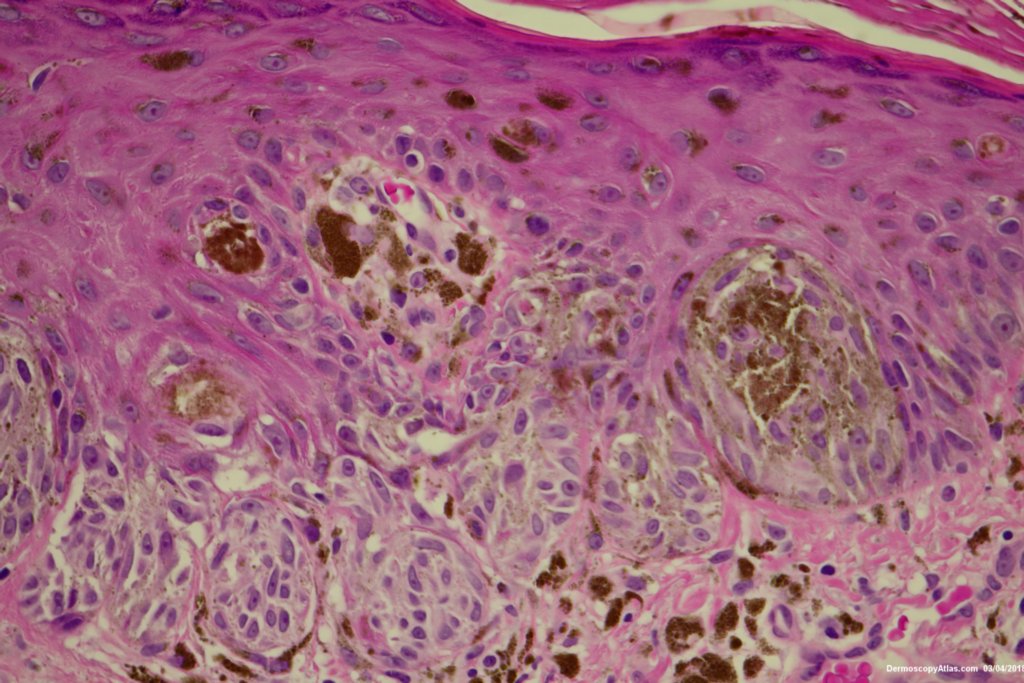

Diagnosis: Reed nevus

Sudden onset of a new pigmented lesion on the shoulder. Dermatoscopy shows an actively proliferating lesion with peripheral pseudopods that involve most of the circumference. Clinically this was either a Reed nevus or a Spitzoid melanoma. The histology favours a Reed nevus.